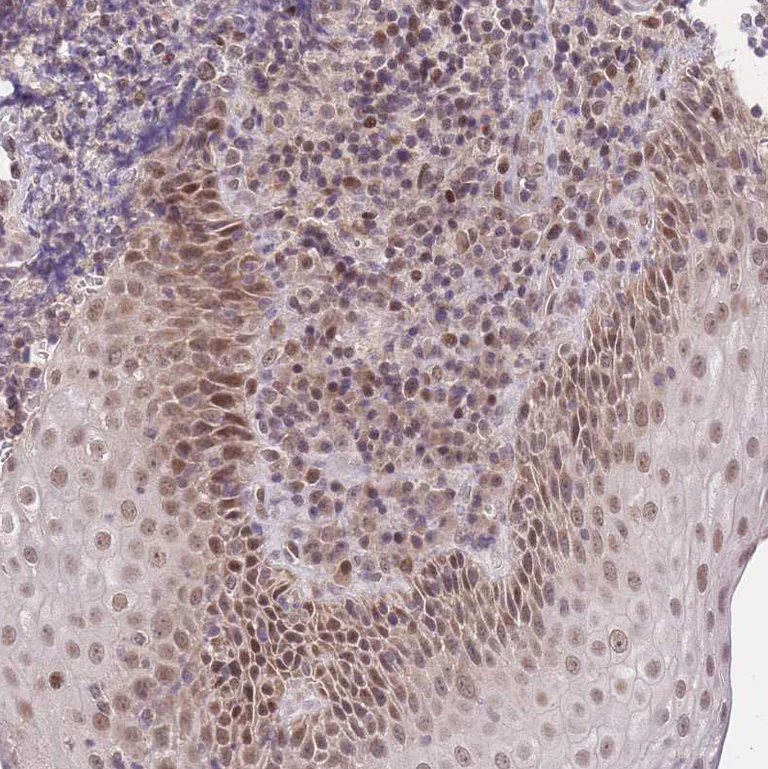

Immunohistochemistry analysis of human tonsil tissue labeling PUS10 with ab185078 at a 1/50 dilution.

Moderate nuclear and cytoplasmic positivity in squamous epithelial cells.

Performed heat mediated antigen retrieval with citrate buffer pH 6 before commencing with IHC staining protocol.